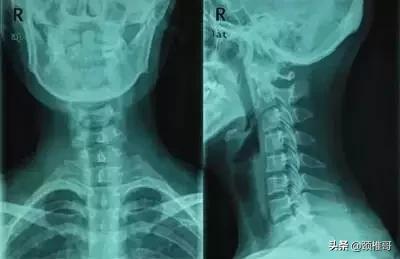

颈椎反弓(比强直更为严重的颈椎疾病)相比强直的颈椎,反弓的颈椎曲度是个反C型,而正常曲度应该是正C型。颈椎有正常的生理弯曲,如果没有生理弯曲,甚至向相反的方向弯曲,称为反弓。

我国颈椎病近十年来发病率呈直线上升趋势。据不完全统计,全世界每天近一亿人发生颈肩臂痛,该症状群已成为骨科门诊最常见的问题。“颈椎反弓”现象在普通X光片甚至医生的体检中都很容易被发现,近年来逐渐呈低龄化趋势。曾发现6岁颈椎就出现反弓的患儿,想必这一现象在中、小学生亦不在少数,严重影响了青少年的健康发育,应引起老师和家长的高度重视。

卧床看书、看电视,高枕卧床看书,睡觉时不适当使用“高枕”,卧高靠背看电视以及长时间上网、搓麻等不良的生活习惯,使头部前屈,导致其曲线前凸日渐减少,变直甚或反弓。“颈椎反弓”现象在普通X光片甚至医生的体检中都很容易被发现,近年来逐渐呈低龄化趋势,应引起低头族的重视。